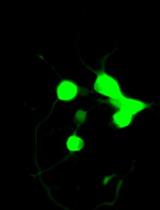

We previously used ginger-derived lipid nanoparticles (GDNPs) for orally delivering CD98 siRNA (Zhang et al., 2017) and 6-shogaol (Yang et al., 2021) to treat ulcerative colitis. These studies suggested that GDNPs could overcome the challenges of oral drug delivery. Further, we found that monogalactosyl-diacylglycerol (MGDG), digalactosyl-diacylglycerol (DGDG), and phosphatidic acid (PA) constitute more than 90% of the total lipids of GDNPs (Zhang et al., 2016; Zhang et al., 2017). In this protocol, we will describe how to use these three lipids at the same ratios found in the GDNPs in the synthesis of new lipid nanoparticles (nLNPs) to encapsulate IL-22 mRNA. The nLNP-encapsulated mRNA showed its therapeutic efficacy in one of our recently published studies (Sung et al., 2022).